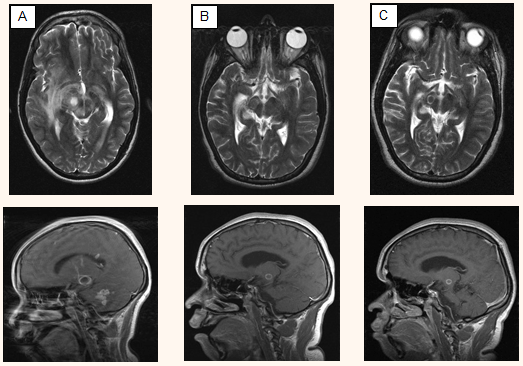

MRI was repeated throughout admission to monitor disease progression. Common signs often present on MRI included leptomeningeal enhancement, ring-enhancing lesions, oedema, abscess and involvement of the brainstem6. This patient developed all of these clinical features throughout his admission, the most prominent of which were the ring-enhancing lesions. Figure 1 illustrates changes as shown by MRI at 3, 6 and 9 months.

Figure 1: Standardized magnetic resonance imaging views showing melioidosis progression. (A) 3 months: Multifocal ring-enhancing lesions scattered throughout both cerebral hemispheres. (B) 6 months: Reduction of oedema in both cerebral hemispheres. Ring-enhancing lesion within the right cerebral peduncle smaller than previously. (C) 9 months: Ring-enhancing lesions remain, with noticeable reduction in size, especially within the cerebral peduncle.